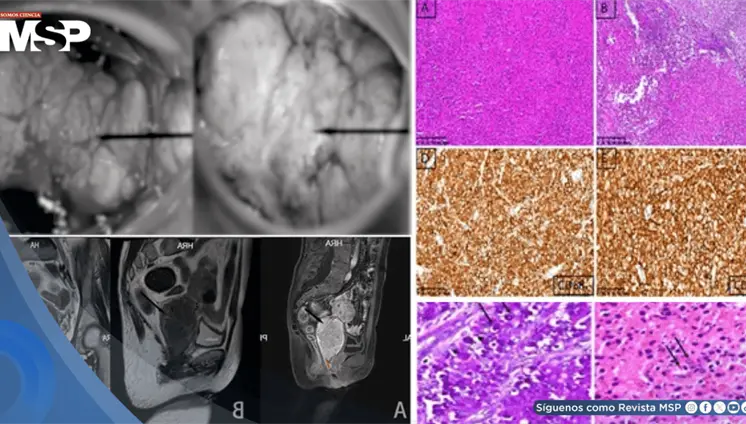

La mujer de 71 años, con antecedentes de histerectomía total y salpingooforectomía izquierda hace 30 años, presentó distensión abdominal progresiva y aumento de peso durante cuatro años.

Las imágenes sugerían infiltración linfomatosa, pero la esplenectomía ...

La paciente presentaba múltiples factores de riesgo incluyendo uso de ...